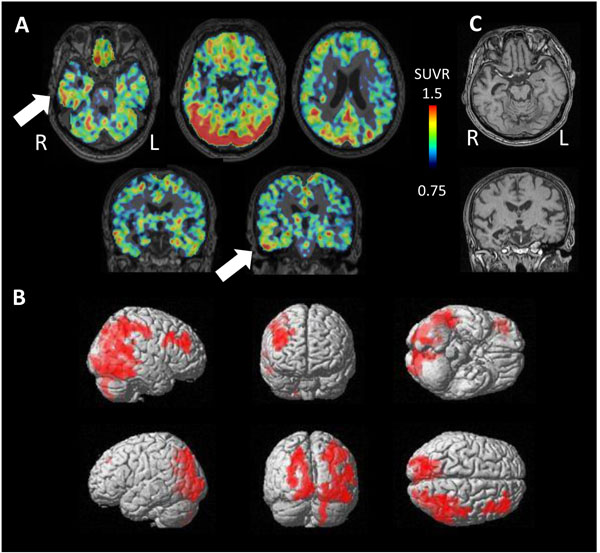

3.4. Autopsy Case

PET study revealed tau accumulation at the right lateral temporal lobe, frontal lobe and, parietal lobe (Fig. 4A,B). Cortical atrophy was predominant on the left side (Fig. 4C), where an apparent accumulation of tau was less severe.

Pathologically, a very limited number of senile plaques immunopositive for Aβ11-28 were found in the temporal lobe (Fig. 5A), occipital lobe and parietal lobe (Fig. 5B; Braak amyloid stage A). Neurofibrillary tangles were scattered in the parahippocampal gyrus (Gallyas-Braak silver staining, Fig. 5C; Braak neurofibrillary stage II) and were immunopositive for AT8 antibody (Fig. 5D) [16, 62, 63]. Neither argyrophilic grain, Lewy body, nor TDP-43 positive structure was found. In conclusion, pathological diagnosis was mild ageing change.

4.2. Pathological Mechanisms for Tau Accumulation

An autopsy was obtained in only 1 case, in which neurofibrillary tangles were observed at the parahippocampal gyrus. [11C]PBB3-PET also revealed tau accumulation in the same lesion. Three cases of clinical NFTPD showed significant [11C]PBB3 accumulation at lateral temporal lobe. These are the typical distributions of neurofibrillary tangle in NFTPD, suggesting the possibility that [11C]PBB3 detects tau in the neurofibrillary tangle in these cases.

Four cases of clinical AGD showed inconsistent results of [11C]PBB3 accumulation, some high and the others low. The side of atrophy does not coincide with that of high [11C]PBB3. High accumulation of AGD may induce cerebral atrophy, but further atrophy may reduce apparent tau accumulation, even below the level of the opposite side. Partial volume effect might enhance this apparent reduction on [11C]PBB3 images. Similar effects of cortical atrophy on apparently less tau accumulation may explain the opposing laterality in the autopsied case.